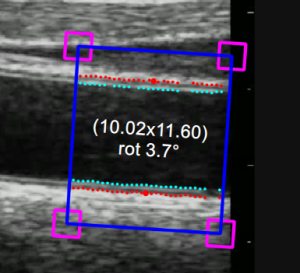

ROI b-mode

La regione di interesse (ROI - Region of Interest) b-mode è la porzione di immagine nella quale vengono calcolati sia il diametro che l'IMT. I punti relativi alle interfacce Lumen-Intima e Media-Avventizia vengono visualizzati all'interno della ROI rispettivamente in turchese e in rosso. La ROI può essere spostata e/o ridimensionata. Ogni volta che si modificano la posizione e/o le dimensioni della ROI, l'analisi viene nuovamente inizializzata.